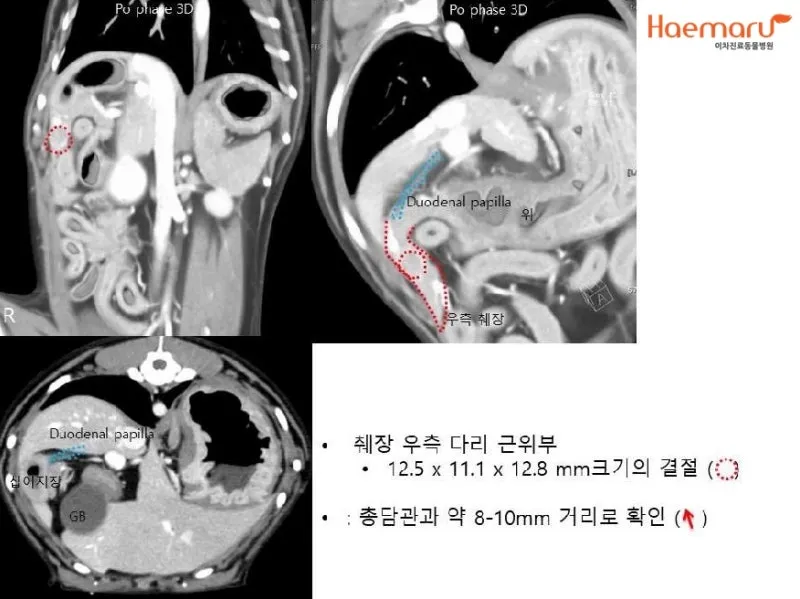

CT와 MRI 검사 - 초음파에서 의심스러운 소견이 발견되면 더 정밀한 검사를 진행해요. 특히 3D 영상으로 종양의 정확한 위치와 크기를 파악할 수 있어서 수술 계획을 세우는 데 필수적이에요.